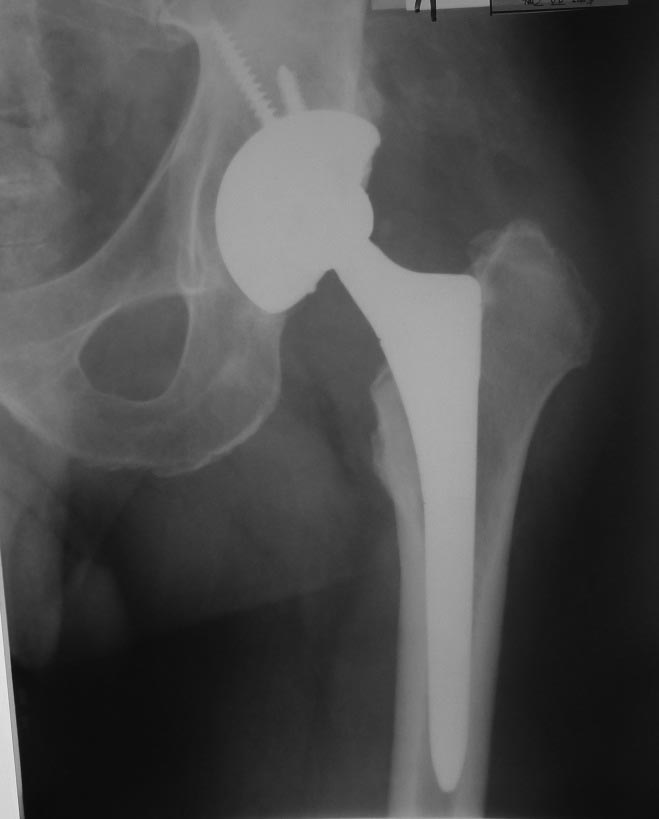

Уважаемые коллеги. В сообщении от 02 июля 2013 г. я уже писал об этом случае. Эндопротезирование пациенту 49 лет выполнил в 2007 г. по поводу коксартроза. В начале мая 2013 г. в состоянии запоя он упал со скамейки, после чего отметил припухлость в области паха и левой ягодицы. За помощью обратился почти через 2 мес. При пункции было удалено около 200 мл стерильной гноеподобной жидкости из области эндопротеза. За несколько дней жидкость снова набралась. 04.07.13 произведена санация гнойной полости с последующим вакуумированием раны. Во время операции признаков нестабильности и износа компонентов протеза, а также дебриса выявлено не было. Заменить полиэтиленовый вкладыш не удалось из-за неисправного запорного механизма. 08.07.13 выполнена пластика раны местными тканями. Дренаж удален через день. На фоне гладкого послеоперационного периода, 17.07.13, вследствие нарушения режима, произошел вывих головки эндопротеза, вправленный в тот же день закрыто. Послеоперационная рана зажила первичным натяжением, выписан 29.07 с рекомендацией ходить в ортезе при помощи костылей с частичной нагрузкой на левую ногу до 1 мес. после вывиха эндопротеза. Через неделю снова «ушел в запой» и был госпитализирован с очередным вывихом протеза. Подобные эпизоды повторялись до декабря 2013 г. еще 5 раз. Каждый раз удалялось до 100 мл стерильной серозногеморрагической жидкости. При последней госпитализации была отмечена гиперемия дистальной 1/3 послеоперационного рубца. Впоследствии пациенту удалось победить порочное пристрастие. Сейчас работает по специальности (водитель), при длительной ходьбе и к концу рабочего дня отмечает дискомфорт или легкую болезненность в области тазобедренного сустава. Наблюдаю его с интервалом в 2-3 месяца. Каждый раз пунктирую область эндопротеза, последние 2 раза жидкости практически не было. СОЭ – 25-40, С-рб до 15-20. Мыслей о замене протеза сейчас нет. Последние (июньские) рентгенограммы – без особенностей (прилагаются). Смущает только обширное синюшно-розовое пятно с отечной кожей (на фото), появившееся в декабре 13 г.: признаком чего оно может являться? Имеет ли прогностическую ценность? Встречался ли кто-нибудь с подобным? Заранее спасибо за ответы.